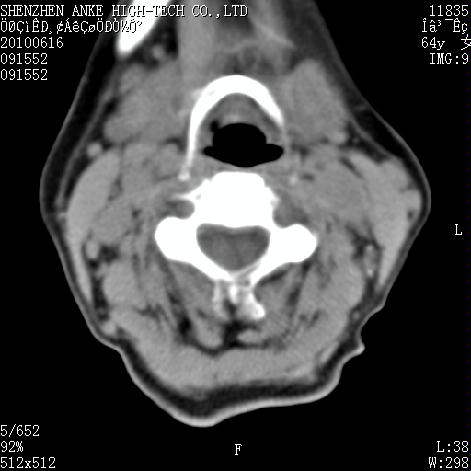

标题: CT27132:患者女,64岁,颈部及全身多处包块,现觉吞咽困难4 [打印本页]

标题: CT27132:患者女,64岁,颈部及全身多处包块,现觉吞咽困难4

右侧甲状腺占位,肿瘤可能性大,癌

右侧甲状腺癌伴右颌下腺淋巴结转移

右侧甲状腺癌伴淋巴结转移

右侧甲状腺癌伴淋巴结转移可能性大

右侧甲状腺癌伴淋巴结转移可能性大。

右侧甲状腺癌伴右颌下腺淋巴结转移!建议增强!